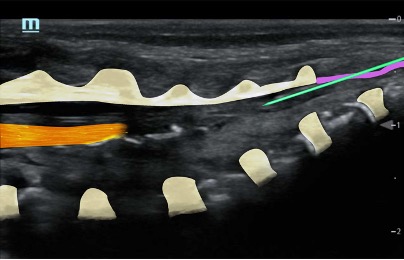

Needle insertion at the apex of the sacral hiatus at an angle of 45⁰ until resistance

Reangle to 30⁰ and insert another 5mm (advance under US vision) – characteristic pop through ligament